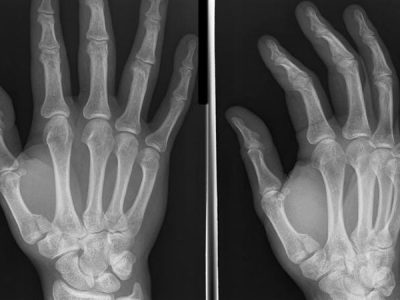

- Hand and wrist

Base of Thumb Fractures Case 35 year old male comes in after a fall whilst playing contact sport. He has pain and deformity to the thumb with gross swelling and bruising. Summary Thumb function constitutes 50% of overall hand…